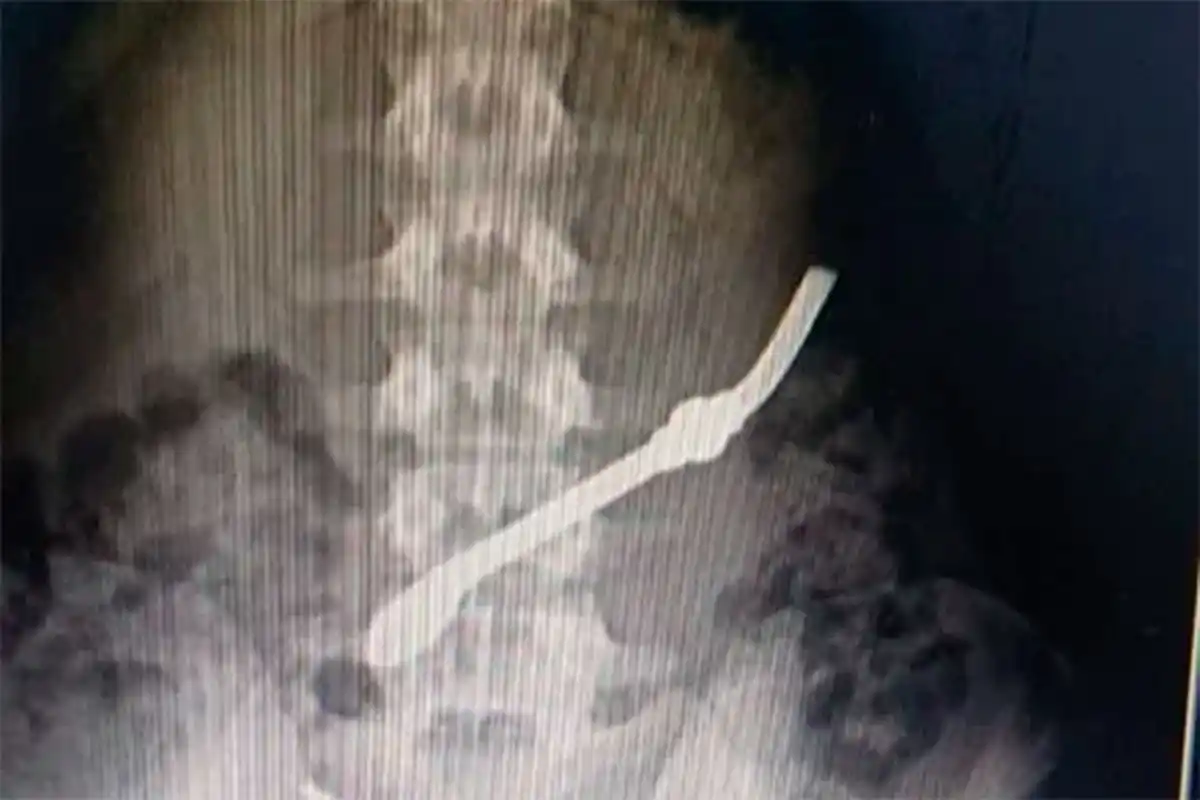

Un interno de la Unidad Penal 7 de Gualeguay fue hospitalizado de urgencia tras ingerir una bombilla metálica como medida de protesta, luego de una disputa familiar. Debido a la gravedad del caso, el hombre fue trasladado inmediatamente al Hospital San Antonio, donde recibió atención médica para evitar complicaciones mayores.

El incidente ocurrió cuando el recluso, alterado porque su pareja no había acudido a visitarlo, decidió autoflagelarse ingiriendo el objeto metálico. La acción generó una situación de emergencia dentro del penal, lo que motivó la intervención inmediata del personal de salud y el posterior traslado del interno al hospital.